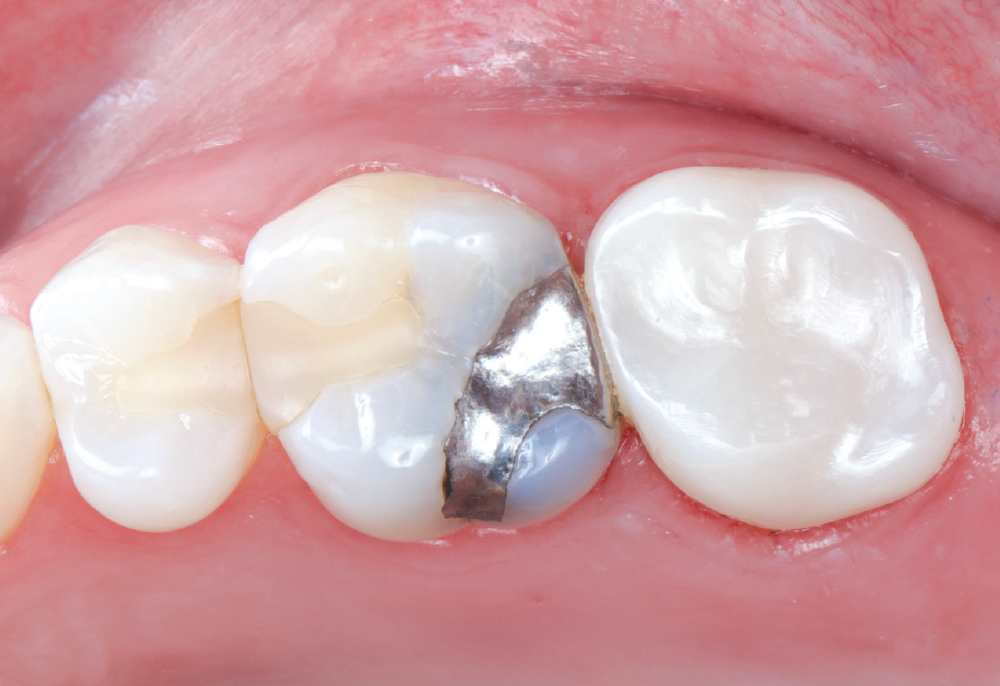

The patient’s chief concern was an open mesial margin of the crown on tooth #15

Figure 1: The patient’s chief concern was an open mesial margin of the crown on tooth #15, which was causing gingival inflammation and shredding her dental floss.

The crown was a 20-year-old Captek™ PFG high-noble bilayered restoration

Figure 2: The crown was a 20-year-old Captek PFG high-noble bilayered restoration.